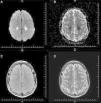

Gadolinium-enhanced MRI of the brain was performed and showed symmetrical hyperintense diffusion-weighted imaging (DWI) signals and decreased apparent diffusion coefficient (ADC) in the parietal lobe white matter, more prominent on the left side, however neither the cortical area nor deep gray matter structures were affected. There was no signal change on FLAIR and T2 images. No abnormality was observed in T1 images (Figure 1). Dynamic susceptibility perfusion imaging showed no evidence of abnormal mean transit time, cerebral blood flow or cerebral blood volume. The absence of vascular or perfusion abnormalities suggests that transient cytotoxic edema of the white matter may be explained by MTX-induced stroke-like encephalopathy.4,5

(A) Diffusion weighted imaging (DWI): symmetrical hyperintense signal in parietal lobe white matter, neither cortical area nor deep gray matter structures were affected. (B) Decreased apparent diffusion coefficient (ADC): symmetrical hyperintense signal. (C) Axial T2/FLAIR image: discreet symmetrical hyperintense signal in parietal lobe white matter. (D) Axial T2: discreet symmetrical hyperintense signal in parietal lobe. No abnormality was observed in T1.